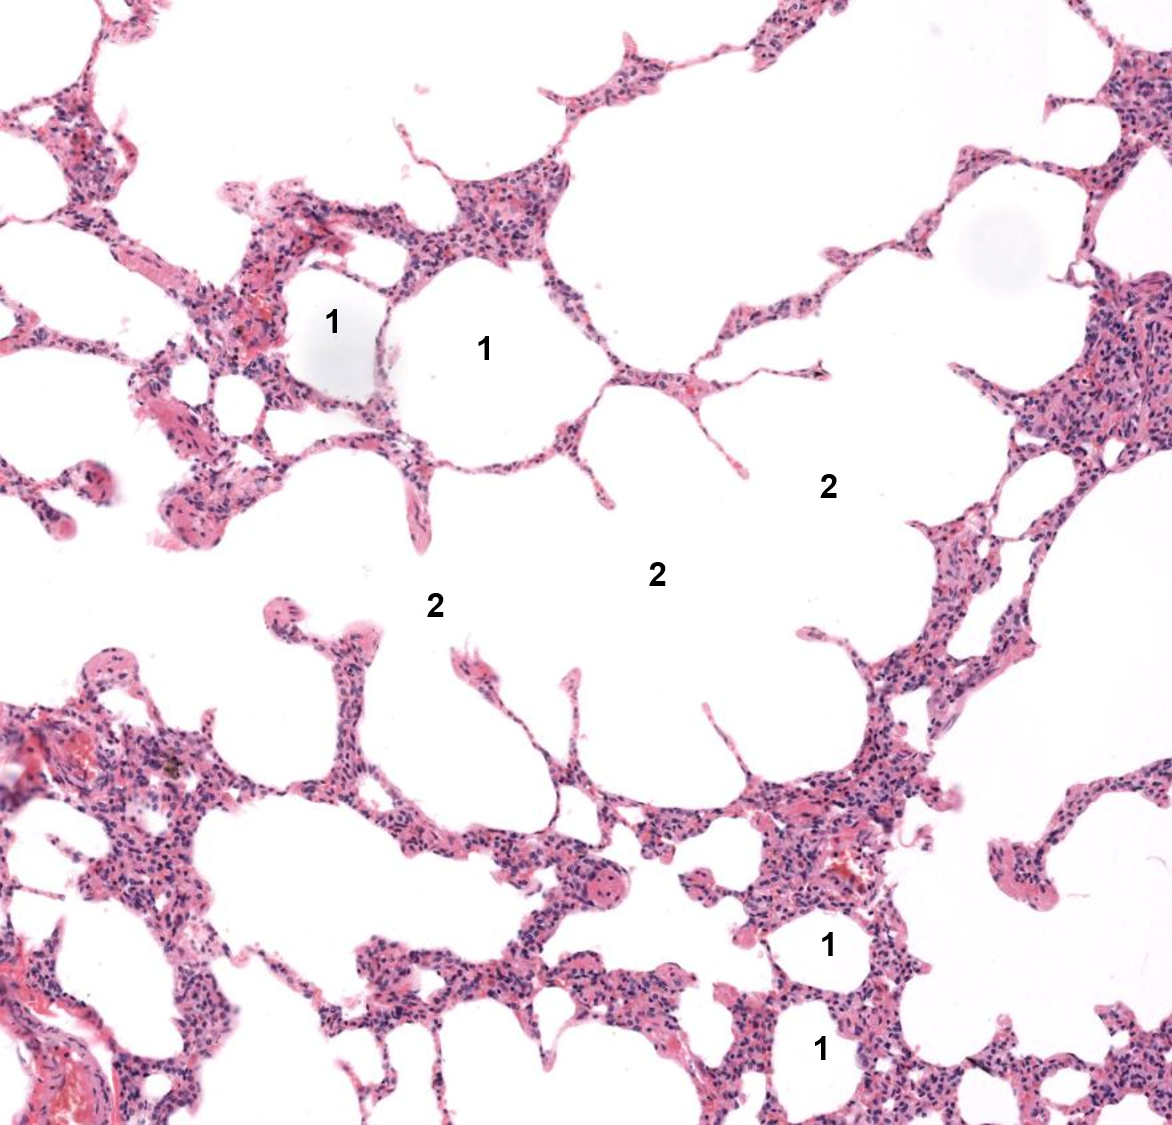

Pulmão

1: Alvéolo

2: Ducto alveolar

1: Saco alveolar

2: Alvéolo